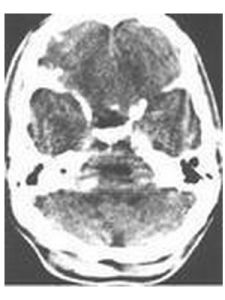

3)CT和MRI:對於脊柱內或顱內的腫瘤可通過CT或MRI檢查發現。腫瘤在CT密度通常較脊髓和腦組織略高,呈圓形或類圓形。在MRI上神經纖維瘤表現為T1上低或等信號,T2上高信號。部分腫瘤伴有囊變。增強掃描後腫瘤多明顯強化。